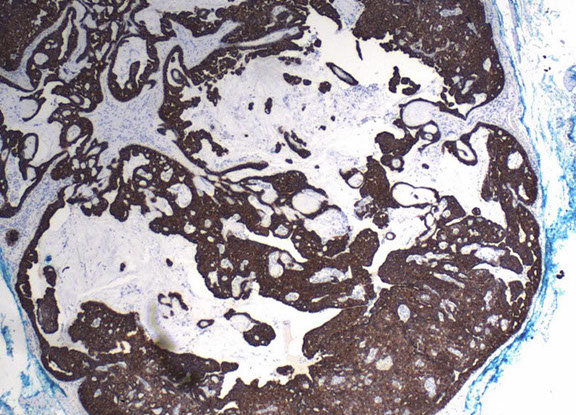

Pilomatrixoma

Trichohyaline granule (which are usually seen in hair shafts) in a pilomatrixoma

- aka calcifying epithelioma of Malherbe

solitary, bluish, firm (often calcifies), benign subepidermal spherical nodule

b9 hair follicle tumor

MC on face of kids or young adults

- 75% of childhood adnexal tumors

- can have multiple lesions in myotonic dystrophy

Sharply circumscribed cyst-like structure in dermis, possibly contiguous with hair follicle (may arise from hair matrix)

- can have inc mits (the malignant form is rare and usually very atypical)

- may have trichohyaline granules (which are usually seen in hair shafts)

3 cell types in fragmented cyst wall:

1) outer layer of blue (basophilic) basaloid martical cells with round nuclei and scant cytoplasm which dies and become dead keratin, which are the ghost cells

- imitate the cells in the root, or bulb of a normal hair follicle

2) mixed zone of eosinophilic cells c large round vesiculated nuclei

3) central zone sheets of keratinized pink "ghost" or "shadow" cells c distinct cell borders and central unstained nuclei

- difference from BCC: basaloid cells undergo abrupt keratinization and form "ghost" cells

Has foci of foreign body reaction, calcifications and ossification in shadow cell lobules

See melanin in shadow cells

Fibrotic stroma infiltrated with granulomatous inflam

Solid nests of basaloid cells may cause misdiagnosis of BCC

Ddx: Basal cell carcinoma c matrical differentiation (differs by continuity with epidermis and abrupt transition into shadow cells without the eosinophilic zone)